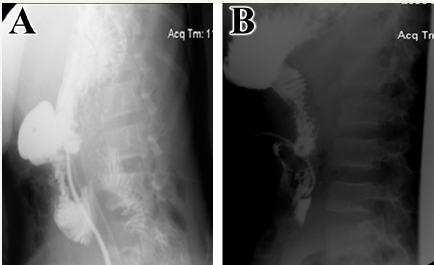

Figure 1: (A) Upper GI series radiography with gastrografin swallow showing significant leak of the contrast material from the lower 2nd portion of the duodenal loop at its junction with the 3rd portion. Two fistulous tracts are demonstrated from this area. The 3rd and 4th portions of the duodenal loop could not be filled. (B) Upper GI series radiography with gastrografin swallow repeated 4 weeks following “triple-tube-ostomy” decompression surgical procedure. Contrast material was injected through gastrostomy tube with no evidence of leak or any fistula from the duodenum. The duodenal loops and upper small bowels show no abnormalities.

The patient returned to the emergency department with sharp abdominal pain on 7th POD. Vital signs showed an elevated body temperature of 38.3℃, tachypnea with 22 breaths per minute, tachycardia with heart rate of 102 beats per minute and hypotesion with a blood pressure of 90/60 mmHg. Patient’s laboratory results were normal except for an elevated white blood cell count of 18,000 cells/μL with 90% neutrophilic count and 11% band cells. Since a leak was suspected, upper gastrointestinal (GI) series was done using gastrografin and showed significant leak of the contrast material from the lower second portion of the duodenal loop at its junction with the third portion (Figure 1A). Patient was urgently re-operated with “triple-tube-ostomy” decompression procedure involving reverse tube duodenostomy, tube gastrostomy, and feeding jejunostomy. Feeding through jejunostomy started on 3rd POD. Following the second operation, patient showed clinical improvement with normal laboratory values. Gastrografin upper GI series was repeated 4 weeks later showing no evidence of leak or any fistula from the duodenum (Figure 1B). Patient was discharged home on 28th POD following the removal of all –ostomy tubes. Currently, the patient returned to his usual state of health prior to the injury, and had an uneventful recovery. Figure 2 represents the case time line.